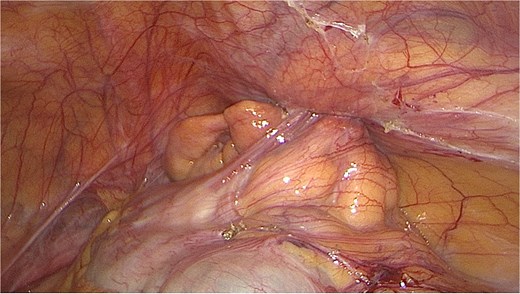

The patient was taken to theatre and a diagnostic laparoscopy was performed. Visual examination intra-operatively demonstrated a right indirect inguinal hernia containing the appendix. The appendix was mildly inflamed and not perforated; however, the mesentery had an ischemic appearance (Fig. 2). Hernia contents were able to be reduced laparoscopically. Due to the appearance of the appendix and mesentery, an appendicectomy. Laparoscopic transabdominal preperitoneal primary repair of the hernia was performed. The patient was discharged from hospital the following day.

Intraoperative image of inflamed appendix within the internal inguinal ring.